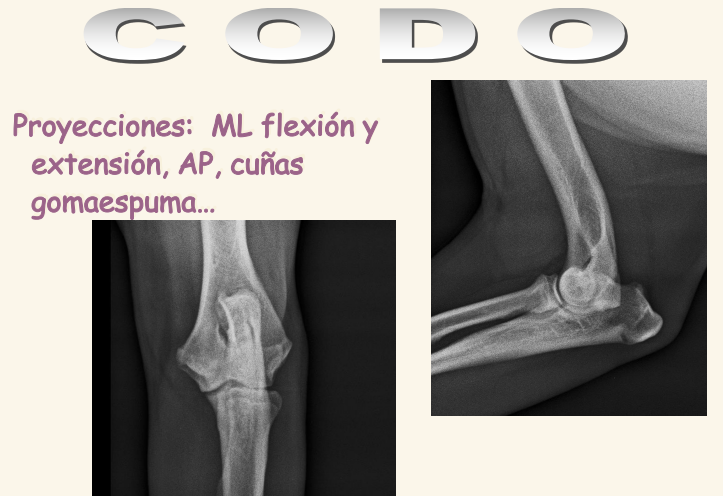

Codo

El condilo medial es mas fuerte que el lateral. Se dan fracciones en T o en Y. Luxacicones son mas dificiles que en codo

Existe la displasia del codo